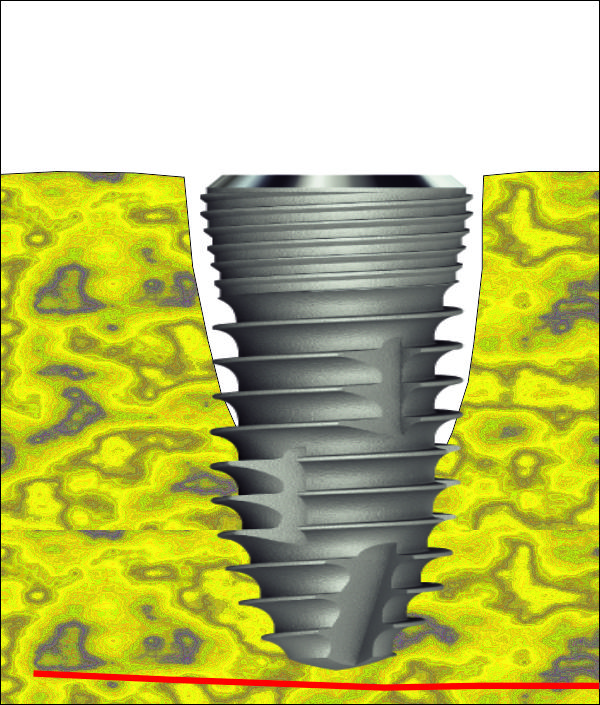

Правилно позициониран зъбен имплант в алвеолата на моларен зъб. Имплантатът е в

центъра на септата и поради това короната няма да бъде изработвана с голям и

асиметричен екватор. Освен това имплантът ще бъде натоварван строго аксиално -

по неговата надлъжна ос. Принципно натоварването под наклон не е съществен

проблем, особено при по-големите

имплантатни размери.

При по-малките размери (какъвто е имплантатът на горната схема) в редки случаи

то може да доведе до провал в

лечението.

Имедиатно поставяне на зъбен имплант с по-голям размер. В областта на

имплантологията е валидно с пълна сила правилото "Размерът има значение".

Очевидно е че имплантът с по-голям размер е в контакт с много по-голяма площ от

челюстните кости. Около имплантатната шийка остава костен дефект само под

формата на цепнатина; колкото е по-малък костният дефект, толкова по-добра е

прогнозата при различните методи за костна пластика. В много случаи дори няма

необходимост от поставяне на изкуствена кост около шийката на зъбния имплант -

например при дефекти с ширина под 1 мм.

Поставянето на широки

импланти още повече подобрява прогнозата на имедиатното имплантиране. При

екстракция на премоларни зъби и резци в много случаи един широк имплант може да

изпълни цялата костна алвеола, при което не остава никакъв дефект и няма

необходимост от костна пластика. При моларните зъби това се случва доста

по-рядко, но е възможно да се получи на практика - особено при импланти с

диаметър от 6 или 7 милиметра, каквито предлага южнокорейският производител

Neobiotech. Широкият имплант има отлична прогноза във

всяка една ситуация - той има голяма устойчивост спрямо напречно и косо

действащи дъвкателни сили.